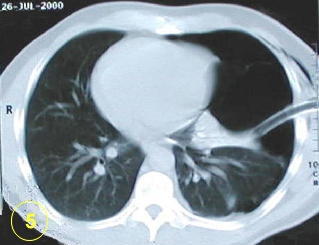

La tomografía computarizada del tórax

y su adecuada interpretación es de gran ayuda diagnóstica

en las patologias del tórax.